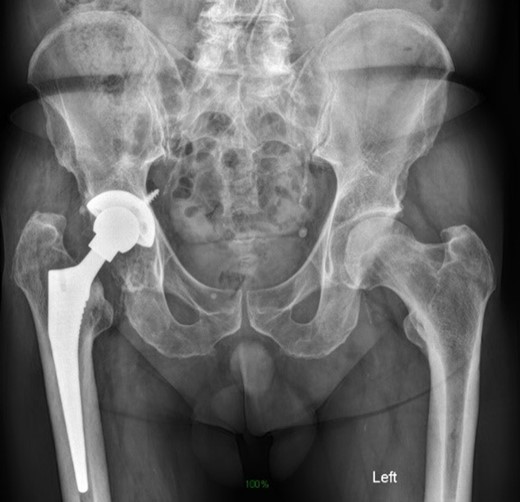

Life-size 3D model was printed from a converted file containing the computed tomography (CT) scan of one patient with severe acetabular defects waiting for total hip revision surgery. The 66-year-old male had a background of coxarthrosis. He underwent total hip arthroplasty of his right hip in February 2017. The preoperative CT scan and X-Ray of the pelvis showed large right-sided pelvic defect and severe acetabular defect (Figs 1 and 2). The patient had history of cardio-vascular comorbidity and underwent 2 week specific antihypertensive therapy preoperatively.

Preoperative radiograph demonstrating large acetabular defect with screw penetration.